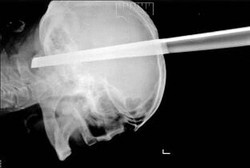

Helen dan James begitu khawatir dengan keadaan putranya yang berusia dua tahun, Ewan Delap. Sebab Ewan kesulitan bernapas dan mengalami mengi. Bergegas orang tuanya membawa Ewan ke rumah sakit. Saat pemeriksaan, ditemukan benjolan di tenggorokan Ewan yang ditengarai sebagai tumor.